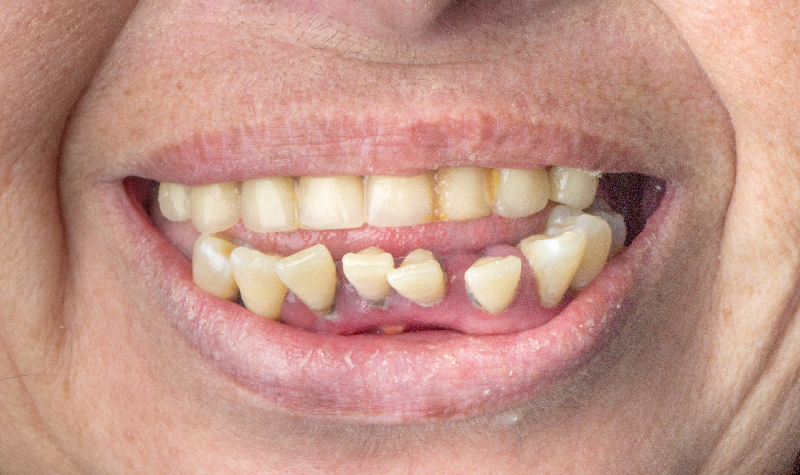

Rehabilitación Oral total con cerámicas sobre dientes e implantes.

Rehabilitación oral total con prótesis inferior sobre implantes y coronas superiores.